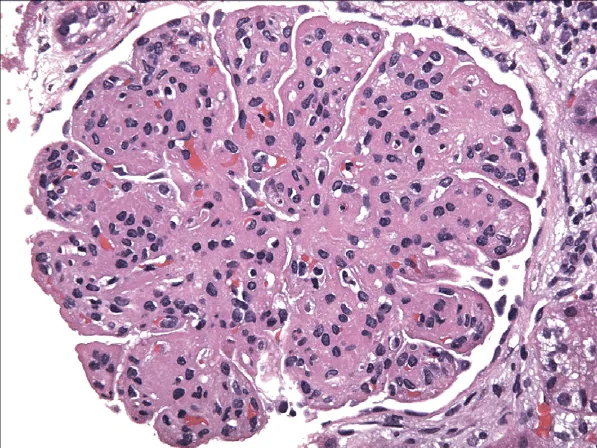

Você sabe quando suspeitar de infecção de cisto em pacientes com DRPAD? Nem toda febre é pielonefrite! Veja os achados clínicos e radiológicos que ajudam no diagnóstico, escolha os antibióticos com melhor penetração e evite falhas terapêuticas. Post indispensável para nefrologistas que lidam com infecção renal em pacientes com múltiplos cistos!

Valkercyo Feitosa